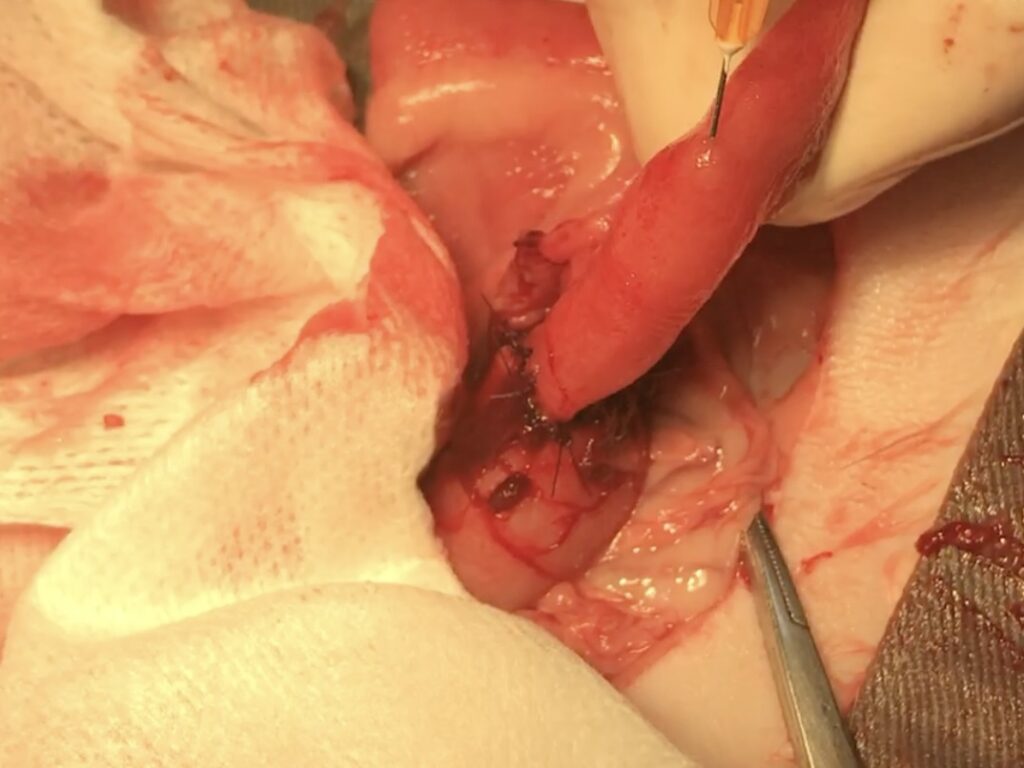

開腹すると、消化管組織が自壊(腫瘍組織が壊死して崩れ、破れて出血や浸出液を伴っている状況)していました。

自壊しいたシコリを切除し、消化管の断端を繋ぎ合わせた後、縫合の確認(リークチェック)を行いました。

手術時には患部周囲に炎症が波及しており、術後回復が順調に行くかととても心配な状況で、ドレーンを腹腔に設置し、手術終了としました。手術後、お腹の中で出血や炎症を確認するためにドレーン(下の画像でグルグル巻の管)をお腹に固定してします。